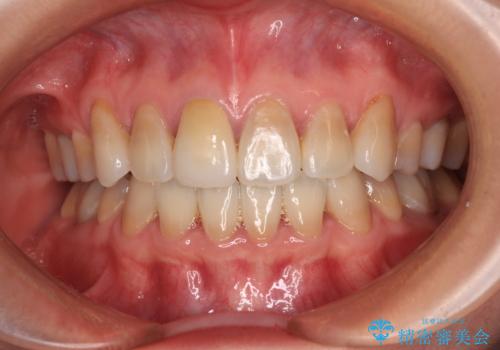

神経組織が健全な状態で残っている歯であったため、1ヶ月かからずに治療を終えることができました。